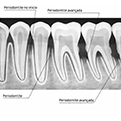

A doença periodontal é uma doença que vem de maneira silenciosa, levando vários anos de evolução, até a perda do dente sem o paciente perceber. Inicia-se com uma gengiva inflamada, com sangramento ao escovar e uso do fio dental. É conhecida como gengivite. A gengivite não tratada leva ao aparecimento da periodontite, onde há uma destruição do osso de sustentação, levando à mobilidade e consequentemente a perda dos dentes. Portanto, a prevenção e o tratamento da gengivite reduzem o risco de desenvolvimento da periodontite. Na foto abaixo podemos ver o lado esquerdo sem doença periodontal e o lado direito com os tártaros e uma grande destruição óssea.